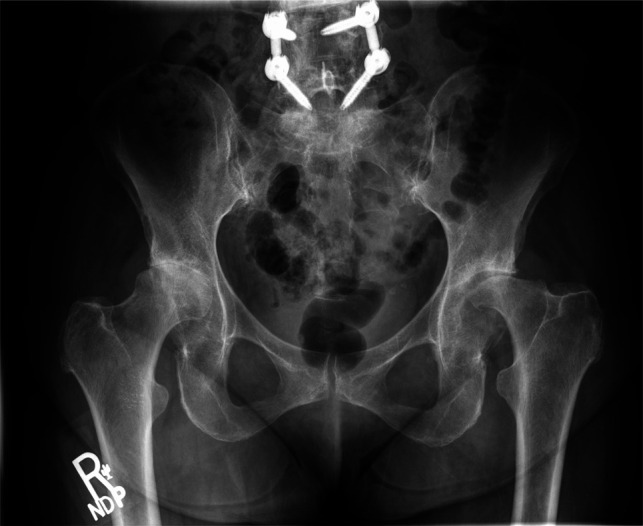

摘要非外伤性双侧股骨头坏死(ONFH)是一种罕见的现象,其病因尚未完全了解。在本报告中,我们描述了一例75岁的女性患者,在关节内皮质类固醇注射后发展为快速发作的双侧ONFH。患者接受分阶段双侧全髋关节置换术。术后几个月,患者出现左侧股骨假体无菌性松动,需要对其股骨假体进行翻修。在最初的手术处理中,她的骨坏死的严重程度和远端程度并没有得到充分的认识,这可能增加了她股骨植入物骨整合失败的风险。本病例表明,关节内皮质类固醇注射可导致严重的ONFH,并延伸至股骨近端并导致固定失败。因此,股骨近端骨坏死的程度可能影响茎的选择。

Atraumatic bilateral osteonecrosis of the femoral head (ONFH) is a rare phenomenon whose etiology is not fully understood. In this report, we describe the case of a 75-year-old female patient who developed rapidly onset bilateral ONFH after intra-articular corticosteroid injections. She was treated with staged bilateral total hip arthroplasty. Several months post-operatively, she developed aseptic loosening of the left femoral implant and requiring revision of her femoral implant. The severity and distal extent of her osteonecrosis was not fully appreciated upon initial surgical management, likely increasing her risk of failure of femoral implant osseous integration. This case demonstrates that intra-articular corticosteroid injections can cause severe ONFH with extension into the proximal femur and fixation failure. Thus, the extent of osteonecrosis in the proximal femur may influence stem choice.